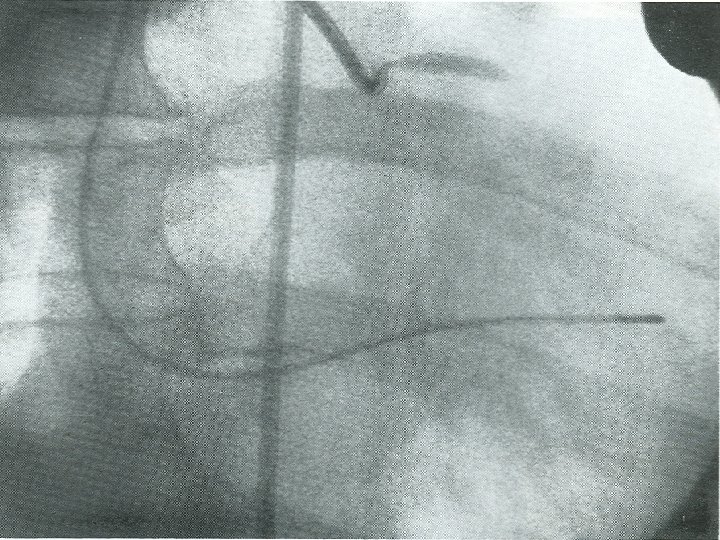

The first coronary angioplasties in Zurich • Stiff wire with a C-shaped tip introduced

The first coronary angioplasties in Zurich • Stiff wire with a C-shaped tip introduced through a plastic catheter (arrow) into the leg artery of a dog